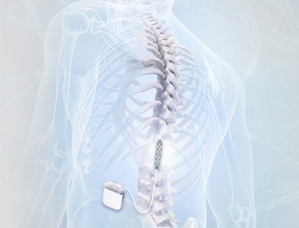

In this study, the researchers provided the results of the STIMO (STImulation Movement Overground) study. In their report, they presented the use of an implanted pulse generator to deliver trains of selective stimulation to the lumbosacral spinal cord (the lower region of the spine which controls leg muscles) in people who had suffered spinal cord injuries. This selective stimulation is called epidural electrical stimulation.

What is epidural electrical stimulation?

Epidural electrical stimulation was introduced in the 1970s to help alleviate abnormal muscle tightness due to prolonged muscle contraction in Multiple Sclerosis (Click here to read more about this). We spoke about the epidural space above in our description of the spinal cord. Epidural electrical stimulation involves a stimulating electrode, which has an array for different stimulating points:

A stimulating electrode. Source: Epiduralstimulationnow

This stimulating electrode is surgically placed in the epidural space so that the stimulating pads of the electrode are facing the spinal cord:

Source: Epiduralstimulationnow

The electrode is then connected to a stimulator which can be programmed to provide very specific patterns of stimulation to the area of the spinal cord where the electrode has been placed.